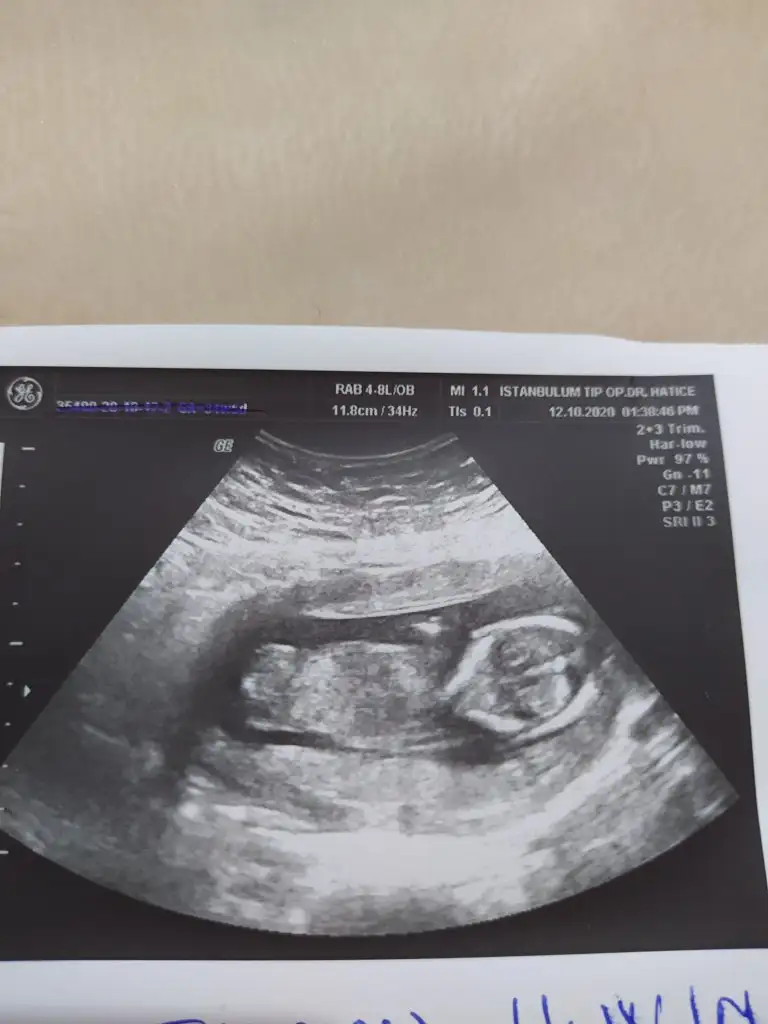

Ya bana da kız gibi geliyor bizimki. Sizin doktor tahminde bulundu mu?